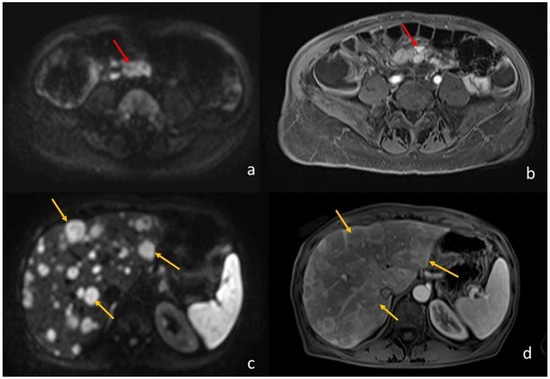

Figure 3.

A 64-year-old woman with ileal NET and liver metastases. (a) (axial DWI b1000) and (b) (T1-weighted image post-Gadolinium injection) shows the ileal NET (pointed by the red arrows). (c) (axial DWI b1000) and (d) (T1-weighted image post-Gadolinium injection) show the multiple liver metastases (the yellow arrows point to the biggest three).